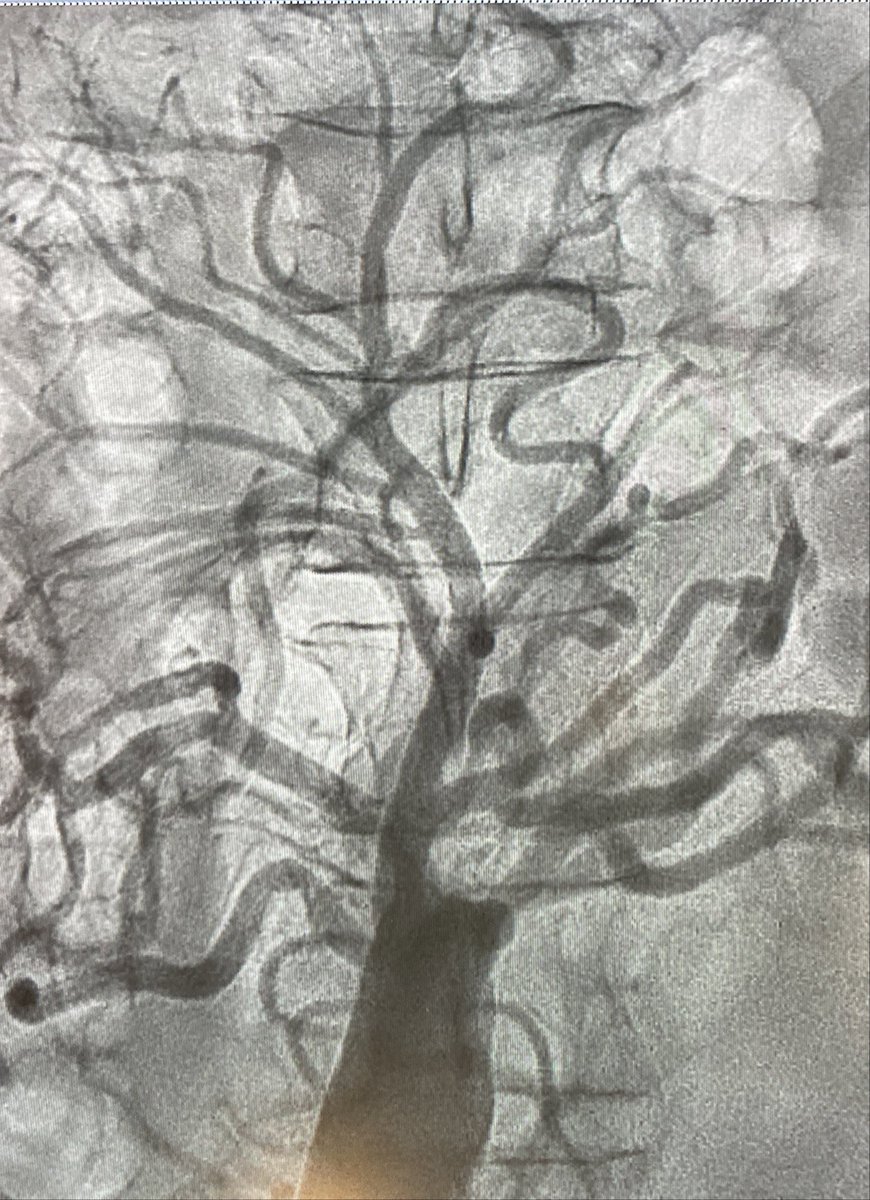

Life’s tree (or Rene Leriche overturned😜) Sometimes may happen in cath lab to diagnose it!